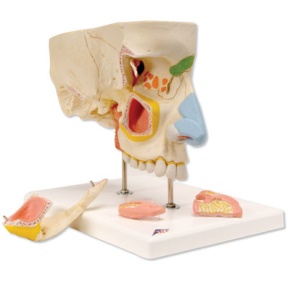

Nase mit Nasennebenhöhlen, 5-teilig

Nasenmodell mit Nasennebenhöhlen, 5-teilig